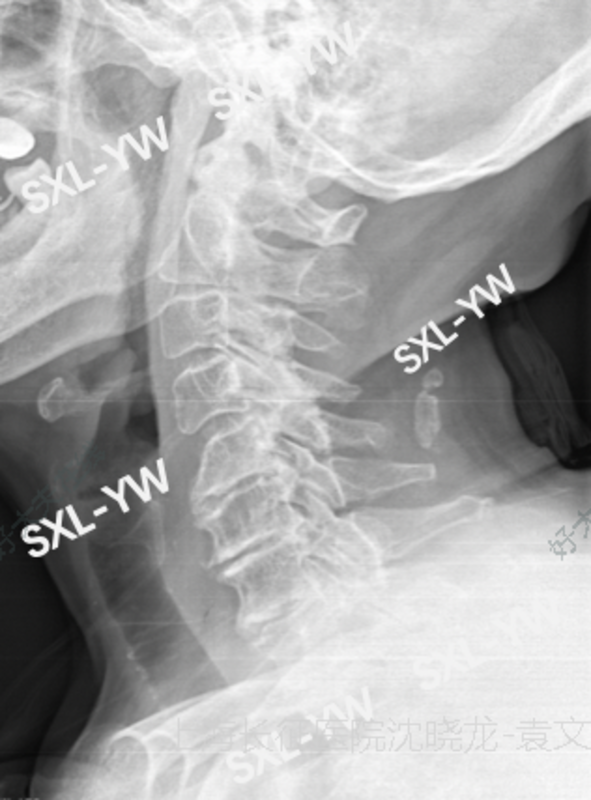

术前X线提示:严重颈椎退变,多节段椎间隙高度塌陷。